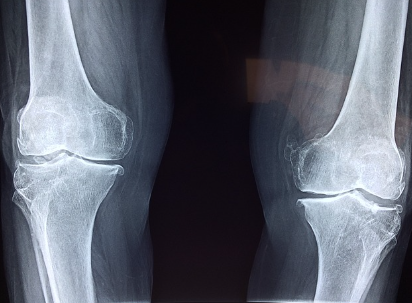

콘드로이친은 관절 연골을 구성하는 중요한 성분으로, 관절의 수분 유지와 탄력성을 증가시키는 역할을 합니다. 특히, 콘드로이친 1200mg은 관절 통증과 염증을 감소시키는 데 효과적이며, 장기적인 복용을 통해 관절의 기능을 향상시킬 수 있습니다. 관절염 환자에게 콘드로이친 1200mg 복용은 통증 완화뿐만 아니라 연골의 감소를 억제하고 염증을 줄이는 데 도움을 줄 수 있습니다.

콘드로이친의 효능은 여러 연구를 통해 입증되었습니다. 예를 들어, 하루 콘드로이친 1200mg을 복용하는 것이 관절 통증 감소에 효과적이라는 연구 결과가 있습니다. 콘드로이친 1200mg은 특히 관절의 염증을 완화하고, 관절 연골의 건강을 지원하는 데 중요한 역할을 합니다.